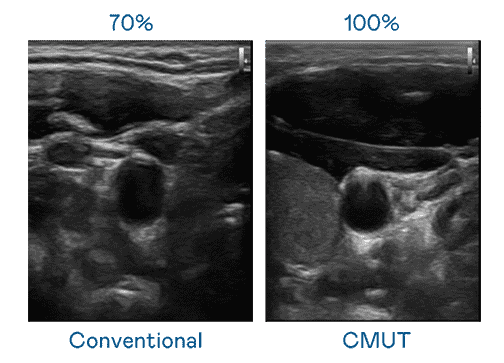

CMUT 技术是一种用电容式微机电元件来产生超音波讯号的技术。。。。与传统 PZT 压电式技术相比,,,CMUT 频宽增加 30%,,,更宽频的超音波讯号让影像解析度大幅提升,,,,是实现高影像品质医疗超音波扫描、、促进精准医疗发展的关键技术。。。

超音波影像的解析度高低,,,,首先取决于探头能发出的讯号频宽。。。。z6尊龙 CMUT 可提供高清晰的超音波讯号,,,,提供高频宽、、高灵敏度、、、影像纹理细节更高的超音波影像,,,,协助医护人员缩短影像判读时间及利用精准的医疗影像进行诊断。。